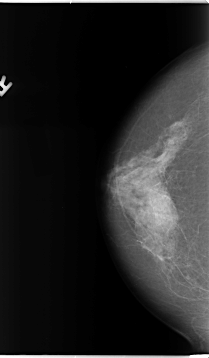

B_3093_1.RIGHT_MLO

B_3093_1.RIGHT_CC

RIGHT_CC LINES 4648 PIXELS_PER_LINE 2712 BITS_PER_PIXEL 12 RESOLUTION 50 NON_OVERLAY

RIGHT_MLO LINES 4712 PIXELS_PER_LINE 2624 BITS_PER_PIXEL 12 RESOLUTION 50 NON_OVERLAY